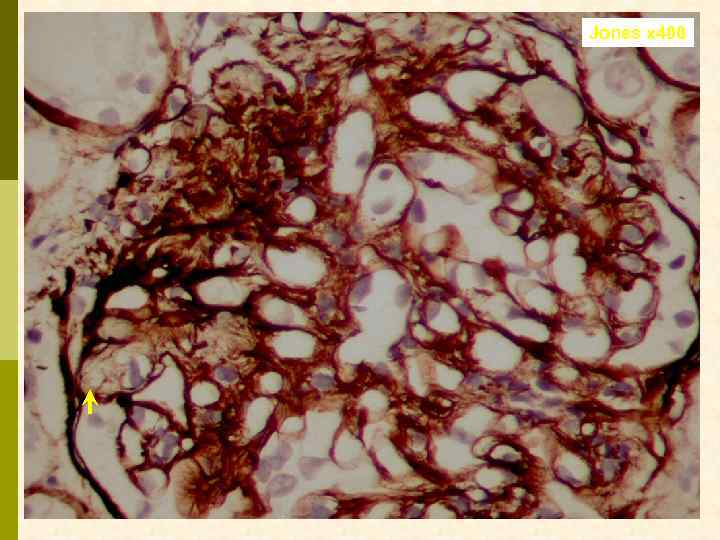

Jones x 400

Jones x 400

Предварительное гистологическое заключение: p Мембрано-пролиферативный, HCV-ассоциированный, криоглобулинемический(? ) гломерулонефрит с полным склерозом 47% клубочков, сегментарным склерозом 22% клубочков и формированием полулуний в 15% клубочков; p диффузно-очаговый выраженный острый канальцевый некроз; p выраженный артерио-артериолосклероз. Примечание: Криоглобулинемическая природа поражения будет уточняться при ЭМ-исследовании.

Заключение p Мембрано-пролиферативный гломерулонефрит, криоглобулинемический, ВИЧ-ассоциированный, на фоне гепатита С